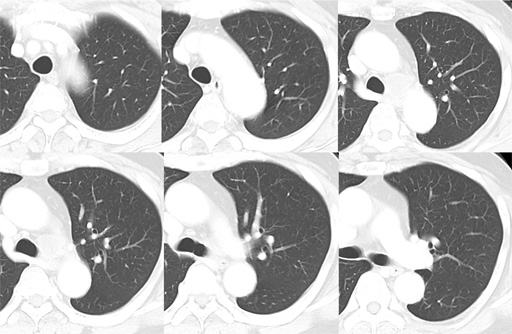

症例7 : 図6 胸部CT 肺野条件